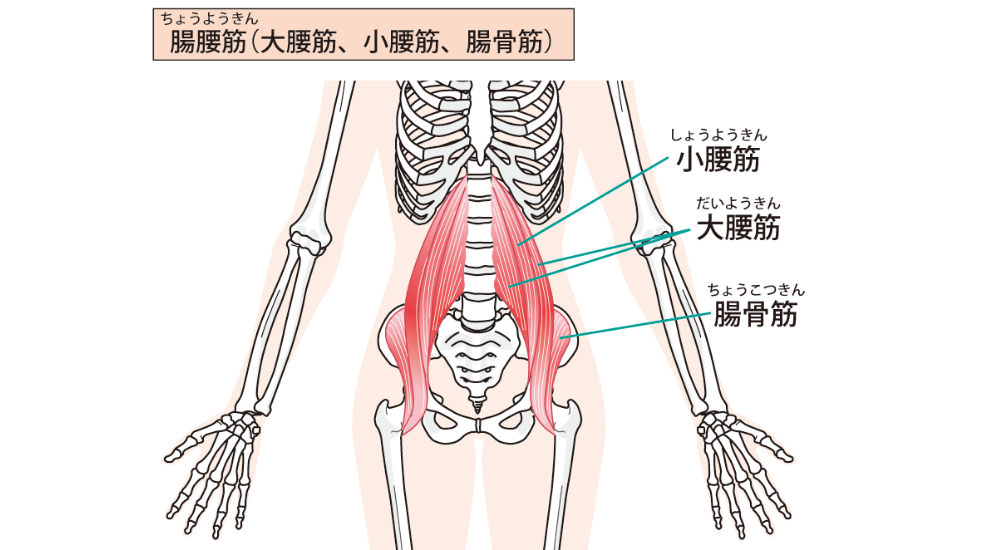

- 腸腰筋(大腰筋・小腰筋・腸骨筋):

腰椎から股関節にかけて走行するインナーマッスルです。長時間座ることで縮こまりやすく、反り腰を誘発し、腰痛の原因となることがあります。